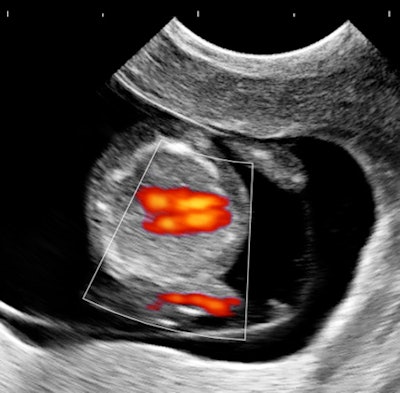

Case 1: Pregnancy, day 64

My own private practice has some routine scanning from local physicians and second-opinion scanning from a much wider geographic zone. Most of the "abnormal NT" cases I used to see were just normal embryos resting supine on the amnion. A recent case was referred from an infertility practice: an 11.2-week embryo thought to have an abnormal NT. This embryo, having a higher specific gravity than amniotic fluid, was dependent in the sac, resting on amnion. Here are an endovaginal view of the neck, an energy Doppler view of the heart, and a 3D survey:

There are multiple cystic hygromas and an apparently normal heart. The 3D really does not look "right" because of a disproportion. No other abnormal findings were evident. We did a cell-free fetal DNA test on maternal blood that established in a few days that this is a case of Trisomy 18.